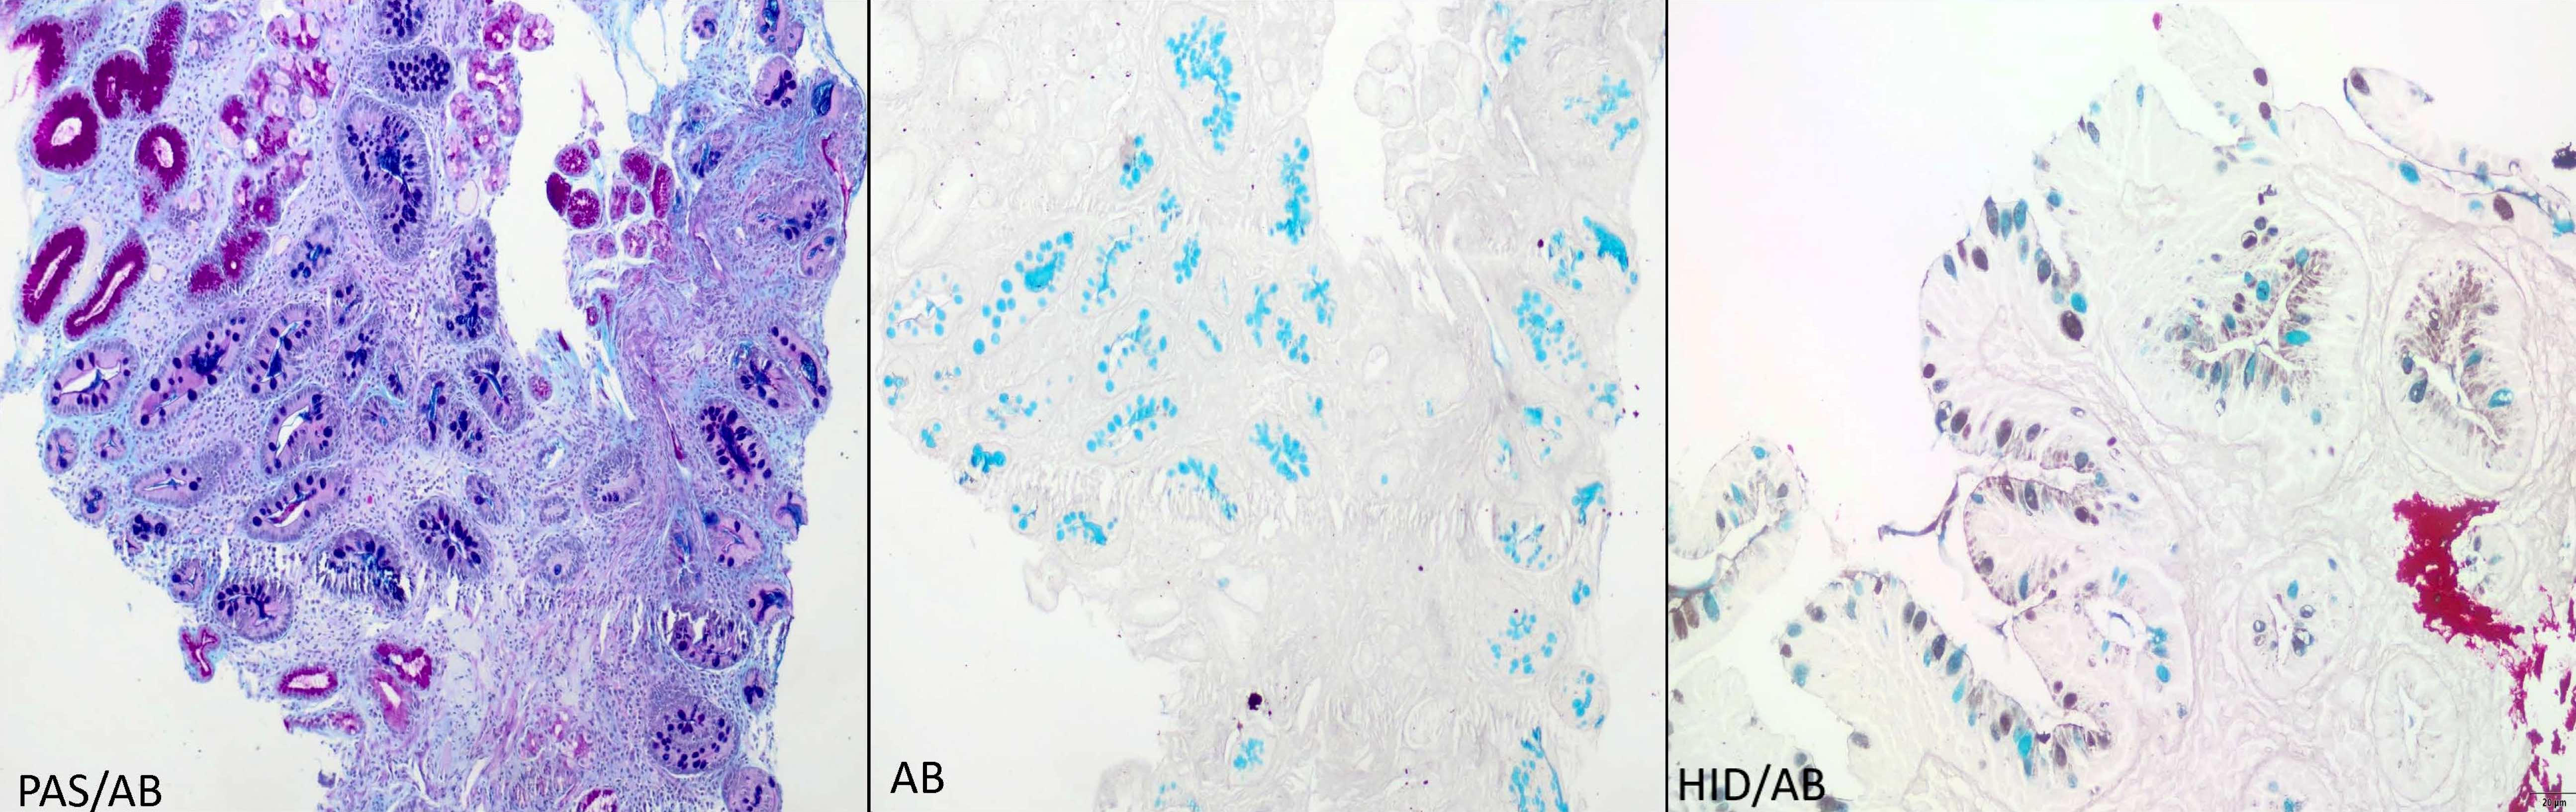

Positive stains

- Alcian blue (AB) at pH 2.5: diagnostic stain but not routinely needed as gastric intestinal metaplasia can be readily identified in H&E; AB stains goblet cells bright blue due to the presence of sialomucins

- Periodic acid-Schiff Alcian blue (PAS AB): stains the acidic or sialomucins as purple and neutral mucins as magenta

- High iron diamine Alcian blue (HID AB): stains the acidic or sialomucins as blue and sulfated mucin as brownish black in color; not routinely performed due to toxic and carcinogenic reagents